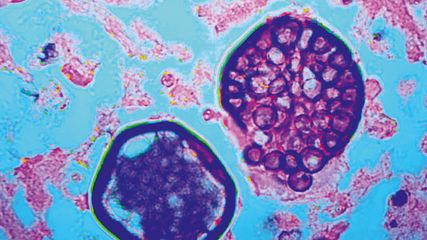

Dabei ist die Auskultation eine einfache Methode, die in der ILD-Diagnostik hohe Aussagekraft hat. Eine aktuelle Studie zeigt, dass das charakteristische Knisterrasseln über den basalen Lungenabschnitten, vergleichbar einem Klettverschluss («velcro crackles»), stark mit dem Bild einer UIP («usual interstitial pneumonia») im HR-CT verbunden ist, welche wiederum den typischen Befund bei einer progredienten ILD darstellt.7